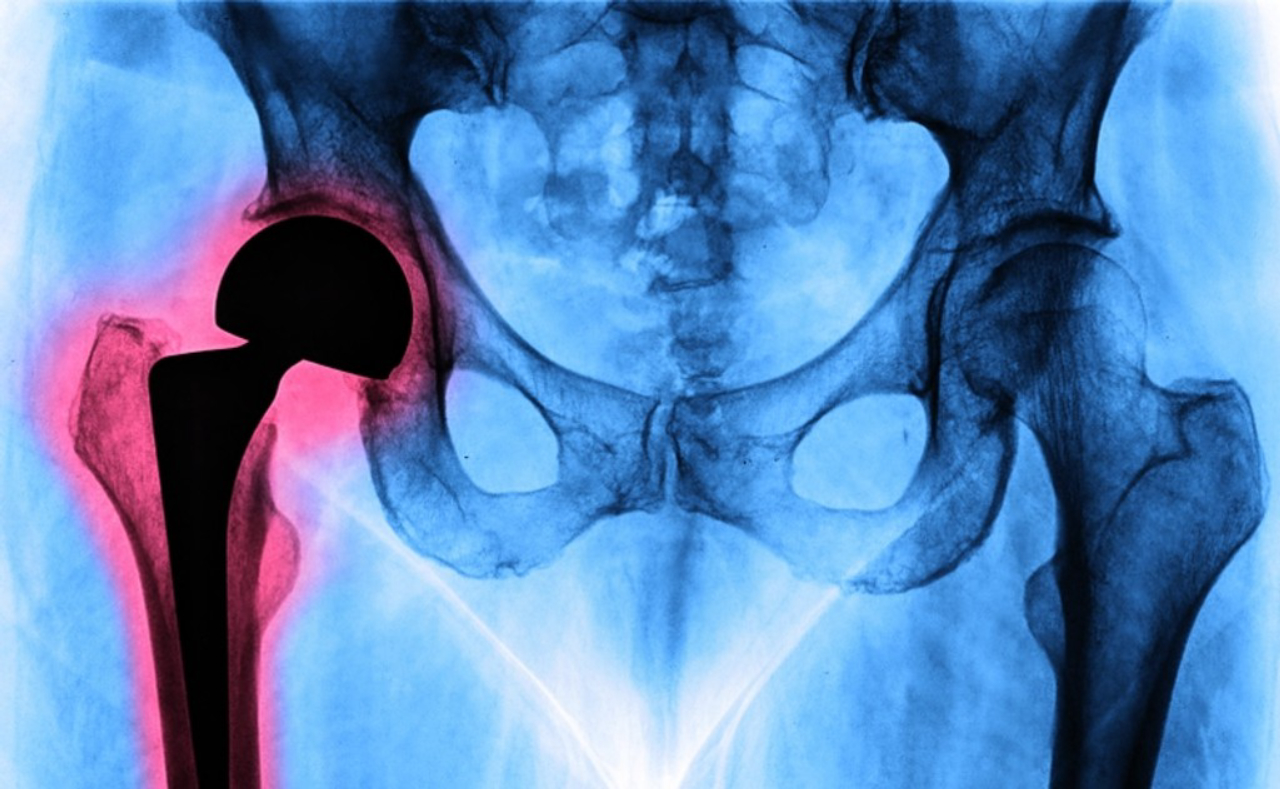

A cirurgia de prótese de quadril -- chamada também de artroplastia de substituição de quadril --, consiste em trocar a articulação do quadril pela prótese. Ela pode ser parcial, quando a cabeça do fêmur é trocada, ou total, quando se substitui também a região da bacia em que o fêmur encaixa, chamado de acetábulo. Apesar de parecer um procedimento agressivo, Pozzi informa que em 95% dos casos os resultados alcançados pela cirurgia são bons.

De tempos em tempos há a necessidade de "trocar as peças". A prótese desgasta em média, em 20 anos, por isso os médicos evitam colocar em pessoas mais novas, pois é quase certo que terá que trocá-la em algum momento da vida.